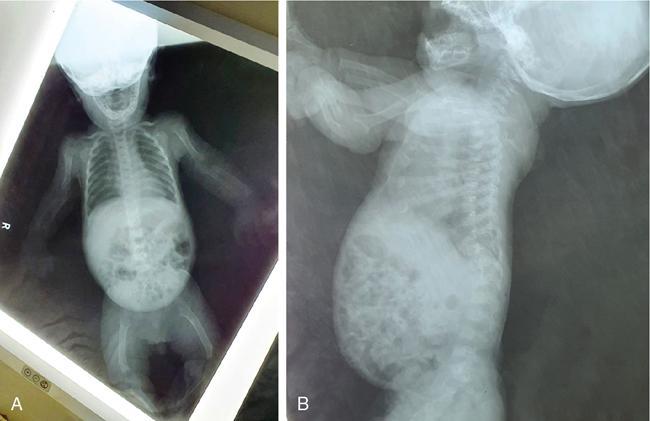

MISCELLANEOUS PAEDIATRIC RADIOGRAPHY – TECHNIQUES AND INTERPRETATION: SKELETAL SURVEY Padma V. Badhe The skeletal survey, generally performed in children, is a set of radiographs done in order to evaluate the entire skeleton. A skeletal survey, commonly used to evaluate skeletal dysplasias, acquired metabolic disorders and suspected child abuse, is still the key radiological investigation for the same. Hence, an explicit understanding of the technique along with the common disorders forms the basis of making a diagnosis in these paediatric pathologies. A skeletal survey is done for various skeletal dysplasias, non-accidental injury (battered baby syndrome) and suspected child abuse. It can also be done in cases of metabolic bone diseases, disseminated infections, multiple myeloma, eosinophilic granuloma. It is also used in evaluation of metastatic bone diseases and polyarticular arthropathy. Orthogonal views of the skull, spine, pelvis and one extremity are taken, preferable in standing position. For preterm babies/newborns, AP and lateral views of babygram may be taken. Projections: For skeletal dysplasias: Additional views: Both extremities may be taken if epiphyseal abnormalities and limb asymmetry is present. Focused views for specific pathologies may be taken. When a diagnosis remains uncertain, 1 year follow up is usually recommended. For preterm babies/newborns: AP and lateral views of babygram may be taken with additional specific views for extremities. For suspected non-accidental injury (NAI): AP and oblique view of chest is taken for better evaluation of the ribs. AP view of abdomen with pelvis. Both upper and lower limbs are evaluated. In lower limbs, two projections in AP and lateral (one with both femur including hip and knee joints; and another for foot and ankle) is taken. AP and lateral views of whole spine, skull. Oblique view of hands. A babygram should be avoided in cases of NAI, as subtle fractures are easily missed. Proper legal documentation while taking the views is very important and ideally two health care professionals must be present. For metabolic disorders: entire skeletal survey is usually not required. Specific views of hands, knees and spine may be taken with additional views depending on the suspected pathology. Centring point: Varies according to the part being examined. Angulation, collimation and orientation: Varies according to the part being examined. Images must be well collimated to obtain lower radiation dose. Detector size: Varies according to the part being examined: 8″ × 10″, 10″ × 12″, 11″ × 14″. Exposure: Ideally high kVp images are taken to reduce radiation dose. But in suspected NAI, low kVp/high mA images are recommended to better demonstrate findings. SID (Source Image Distance):100 cm Grid: Grids are not routinely used to image spine, pelvis, skull and abdomen in children. Radiation dosage: 0.3–3 mSv Essential image characteristics: Adequate spatial resolution, high signal to noise ratio, low kVp (50–70) for high contrast should be done. Excellent bone and soft tissue details are required. The presentation of skeletal dysplasia can range anywhere from minimal stunting of growth and bowing of limbs to severe dwarfism and multiple fractures. Knowledge of the commonly encountered dysplasias with an approach to arrive at a diagnosis is vital in any Radiologist’s practice The following flow chart summarizes the classification of important skeletal dysplasia: The following table summarizes the various dysplasias affecting the axial skeleton: TABLE 7.5.1.1 The following flow chart summarizes the working approach to skeletal dysplasias: Osteopetrosis (Albers-Schonberg disease/Marble bone disease) (Fig 7.5.1.1): Osteopetrosis clinically presents with anaemia/thrombocytopenia or cranial nerve compression. Radiological features include generalized increase in bone density with loss of medullary space. However, cortico-medullary appreciation with cortical thinning is also rarely seen. Bone within bone appearance with Erlenmeyer flask deformity is also noted. Pyknodysostosis (Figs. 7.5.1.2 and 7.5.1.3): patient presents with short stature. Unlike osteopetrosis, there is no anaemia. Radiographs show generalized increase in bone density with preserved medullary canal. There is mandibular hypoplasia with obtuse angle. Acro-osteolysis is also a feature. Dental caries with osteomyelitis of the jaw may be seen. Sclerosing dysplasia presenting as wavy undulating new bone formation. Usually monomelic, lower limb and along one side. The classic appearance is described as Dripping candle Wax sign. It is a Sclerosing dysplasia with radiological features of symmetric juxta-articular involvement in epimetaphyseal region. They are 1–10 mm in diameter and uniform in size. No metabolic activity is seen on bone scans. This skeletal dysplasia shows diffuse decrease in bone density with paper-thin cortex. Fractures heal in normal time but shows callus with poorly cellular matrix. Wormian bones and enlarged sinuses may be seen. Codfish vertebra (Biconcave vertebra) may be seen. Metaphyseal corner fractures are not seen in osteogenesis imperfecta that helps to differentiate it from battered baby syndrome. There are four types of OI out of which type one is most common (Figs. 7.5.1.6 and 7.5.1.7). The radiological features of MPS include Osteopenia and Universal platyspondyly. The intervertebral disc spaces are maintained. Proximal pointed metacarpals is an important radiological finding. Hurler’s syndrome show anteroinferior beaking with short and wide metacarpals. Varus deformity of humerus is characteristically seen in Hurler’s syndrome (Fig. 7.5.1.8). Mental retardation & corneal clouding is seen in Hurler’s syndrome whereas these Hunter’s disease has normal intelligence with no corneal clouding. Morquio’s syndrome shows central beaking (Fig 7.5.1.9). This skeletal dysplasia shows normal bone density with rhizomelic limb shortening and normal trunk. Narrowing of spinal canal is classically seen with decrease in the Interpedicular distance caudally. Other radiological features include trident hand (separation of middle & third fingers), Champagne glass pelvis (short, flat ilia and small sciatic notch), bullet nose vertebra and overexpansion of skull with narrow foramen magnum (Fig. 7.5.1.10). This skeletal dysplasia is characterized by normal bone density with dwarfism and normal craniofacial skeleton. The interpedicular distance is normal. There is severe platyspondyly with anterior tonguing (disappears at older age). Other radiological features include increased disc space, short stubby metacarpals, small irregular epiphysis and widened metaphysis. Anterior tonguing is a feature of Pseudoachondroplasia. This form of skeletal dysplasia involves the spine and epiphyses (Fig. 7.5.1.11). There is normal bone density with rhizomelia. Spine and Pelvis can be involved. Premature osteoarthritis can be seen. The other characteristic features include Platyspondyly and small irregular epiphysis. There are two forms Spondyloepiphyseal dysplasia Congenital and Spondyloepiphyseal dysplasia Tarda. Spondyloepiphyseal dysplasia Congenita is Autosomal dominant and shows pear-shaped vertebrae. Spondyloepiphyseal dysplasia Tarda is X Linked recessive with heaped up vertebrae. It has two forms. The first form is Conradi Hunermann syndrome which is autosomal dominant characterized by asymmetric limb shortening with metaphyseal flaring (Fig. 7.5.1.12). The Autosomal recessive form is Fatal in first few years. Rickets: Rickets refers to deficient mineralization of the growth plate in the paediatric population due to deficiency of vitamin D. In an immature skeleton, there is abnormal mineralization at the zone of provisional calcification in the metaphysis due to osteoid deposition resulting in widening of the growth plate. The features of rickets include fraying, splaying and cupping (Fig. 7.5.1.13). Fraying denotes indistinct margins of the metaphysis whereas splaying denotes widening of metaphyseal ends. Term ‘Cupping’ is used for increased concavity of the metaphysis. These findings are typically seen involving areas of active growth (e.g. distal femur and proximal tibia in the knee) Bowing is a result of associated osteomalacia leading to weakening of weight-bearing lower limb bones. Other bone deformities such as genu valga, genu varum, protrusio acetabuli can also be seen. The lower ribs may also be drawn inwards inferiorly by the attachment of the diaphragm this is called Harrison’s sulcus. Scurvy: Scurvy is a result of dietary deficiency of Vitamin C (ascorbic acid). The classic presentation is that of a patient with an increased bleeding tendency and osteopenia with poor wound healing. Features of scurvy include generalized osteopenia with cortical thinning termed as ‘pencil-point’ cortex. Other radiological findings include the periosteal reaction due to subperiosteal haemorrhage. Expansion of the costochondral junctions occurs forming scorbutic rosary. Bleeding into the joint spaces may result in hemarthrosis. Circular, opaque radiologic shadow surrounding epiphyseal centres of ossification may result from bleeding (Wimberger ring sign) (Fig. 7.5.1.14). Frankel line may be seen. It represents dense zone of provisional calcification. Lucent metaphyseal band is seen underlying Frankel line called as Trümmerfeld zone. Metaphyseal spurs may be seen that result in cupping of the metaphysis (Pelkin spur). Pelkin fracture (metaphyseal corner fracture) can also be seen. Images obtained must be of good resolution with adequate bone and soft tissue details. Additional views: They have already been described in positioning. CT Brain in can be done in cases of NAI to look for subdural hematomas. A skeletal survey is the first-line imaging modality for evaluation of skeletal dysplasia, nonaccidental injury and metabolic bone diseases. The skeletal survey must be tailored according to the respective indication. It helps to characterize syndromic patterns in skeletal dysplasias, with evaluation of complications. In cases of diagnostic dilemmas, additional focused view and occasionally yearly follow-up is recommended. A high index of suspicion is needed in utilizing skeletal survey as a diagnostic modality in NAI. At the same time, one must also remember the legal and social implications of making this diagnosis. BABYGRAM Babygram is a colloquial term used for a radiograph of the whole body of a newborn or just the chest and abdomen (thoracoabdominal babygram) on a single image. As the name suggests it is a rather non-targeted study. It is most commonly requested after line placement. Evaluation of skeletal abnormalities in a deceased foetus is typically performed using anteroposterior and lateral views of a babygram. It helps in pointing out skeletal causes of death in stillborn or dead foetuses. This will help the treating physician and parents understand the reason for baby’s death. This will also help in future genetic counselling of the couple. Sometimes chest or abdominal radiographs of the baby are requested but due to radiographers error or inexperience with small babies, there is inclusion of the region not to be assessed leading to a false babygram. Babygram is most frequently done after line placement in neonates, to view the position of the umbilical vein or artery catheter and to confirm appropriate placement. It is a useful modality in skeletal dysplasias (Fig. 7.5.1.15) like osteogenesis imperfecta, thanatophoric dysplasia and chondrodysplasia punctata. It can also be used for skeletal deformations probably caused by foetus akinesia and in cases of Caudal regression syndrome. In stillborn foetuses, it is used for evaluation of skeletal dysplasias prior to an autopsy (Fig. 7.5.1.16). It is also used in screening for surfactant deficiency and in cases of Necrotizing Enterocolitis in preterm babies where it can help to see the bowel dilatation, intramural and portal venous gas. It can be done in aneuploidies like trisomy 18 and in cases of sudden infantile death syndrome. All the essential equipment and room need to be prepared including the exposure factor. This should be done prior to placing the baby on the table to prevent any neonatal heat loss. Ensure that the baby is correctly identified. Give brief explanation to the patient’s parents regarding the procedure, its risks and benefits. Ensure that the accompanying relative is not pregnant (if female). Parents/guardians/nurses should be instructed to hold the baby with arms above the head and legs straight down. Sandbags/tapes can be used to immobilize the baby. Avoid taking the radiograph when baby is crying. Normal appearance: The endotracheal tube should lie in the lower third of trachea, distance can vary with position of baby’s head. Umbilical artery catheter has an inferior dip along the internal iliac artery, which then turns superiorly along the aorta. The tip should lie in the mid-thoracic aorta (T6–T10) or lower (L3–L4) away from aortic branches to prevent any thrombosis. Umbilical venous catheter does not have the inferior curvature, but rather a posterolateral angulation to the right near the liver through the ductus venosus. The tip should lie in the superior IVC or right atrium at T8/T9 vertebral level (Fig. 7.5.1.17). Portal venous gas may be seen initially after insertion. In a stillborn foetus, the approximate gestation age of the foetus and corresponding ossification centres must be known. In early gestation, the lack of appearance of an ossification centre may be mistaken for skeletal dysplasia. Both chest and abdomen should be included. In a rotated patient, the distance between the spinous process to medial end of clavicles will be asymmetric. The medial end of clavicle should overlap the lung apex, if above, suggests lordotic image. Motion artefacts to be reduced as much as possible. A crying neonate may result in an expiratory film, and hence must be evaluated accordingly. In evaluation of skeletal dysplasias in the newborn, additional views of skull and hand have to be obtained. Baby gram is a useful diagnostic investigation for position of the paediatric umbilical catheters. It helps in general survey in skeletal dysplasia (Fig. 7.5.1.18). It is a simple, effective study in deceased foetus for diagnosis and further counselling, sometimes obviating the need for an autopsy. As baby gram is a non-targeted study, it increases the dose of radiation for the baby. As the exposure settings remain same for the entire body of the baby, the quality of the image decreases. This increases the chances of missing subtle findings. The babygram in a neonate is currently used to localize umbilical catheters. In stillborn fetuses, it is still an important study for documenting and confirming skeletal dysplasias. Understanding the normal appearance as per gestation age and patterns of various common skeletal dysplasias is essential for evaluation. Being a non-targeted study, it should not be used as an alternative study to evaluate the chest or abdomen considering radiation exposure and poorer image quality. INVERTOGRAM Invertogram was first described by Wangensteen and Rice in 1930. It was used as a first investigation to be ordered in evaluation of infants with clinically diagnosed or suspected Anorectal Malformation (ARM). ARM is a serious but surgically treatable congenital malformation with approximate incidence of 1 in 5000 live births. Though the diagnosis of this condition is based on clinical history and physical examination, imaging plays an important role in deciding the type of ARM, and associated complications to aid in management. International classification of anorectal malformations is as follows. Syndromic association is seen as a part of VACTERL defects, trisomy 21 13 and 18, Klippel Feil syndrome, cat eye syndrome etc. The main indication of Invertogram is to evaluate anorectal malformation in a neonate. A radio-opaque marker is placed over the external anal opening. Infant is held inverted by holding both thighs, maintaining this posture for at least 5 minutes before taking an X-ray in true lateral position (Fig. 7.5.1.19). Exposure is made during inspiration. The Invertogram should ideally be done 24 hours after birth as, the rectal gas may not reach the terminal segment if study is done too early. Pubo-coccygeal line (PCL) is drawn from upper border of pubic symphysis (which corresponds to centre of pubic bone on lateral X-ray) to sacrococcygeal junction. I point is the inferior most point of ischial ossification centre. A line which is drawn parallel to PC line passing through the I point is called I line. ‘A’ point is represented by marker placed at anal pit. The position of rectal pouch gas shadow is observed with respect to these lines and appropriate diagnosis is made (Fig. 7.5.1.21). A diagnosis of high ARM is made when gas shadow of rectal pouch is cranial to PCL. If rectal pouch gas shadow is in between PCL and I line, it is called as intermediate ARM and if it is caudal to I line, it is diagnosed as low ARM. Gas in urinary bladder or vagina or beaking of gas shadow of rectal pouch indicates fistula into one of these sites. Associated congenital abnormalities like spinal defects are also looked for in the invertogram (Fig. 7.5.1.22). Invertogram done too early (less than 24 hours) may not demonstrate rectal gas. Meconium plugging the terminal segment gives false position of the rectal gas. Positioning can cause discomfort to child and an irritated crying child actively contracts the sphincter muscles, pushing the gas shadow higher. Rectum may be pulled cephalad due to gravity in inverted position. The rectal gas may escape through an associated fistula. Erroneous interpretation can also occur due to sacral anomalies and when gas in vaginal cavity is misinterpreted as distal rectal gas. Both ischial bones should superimpose and terminal blind loop should be well distended. It is an easily available modality and can be done quickly, does not require additional equipment. It has lesser radiation dose as compared to CT invertogram. It provides a rough guide as to the type of ARM and decides management. Higher localization of obstruction due to various causes like meconium plugging, imaging done too early etc. as described above in pitfalls. It is more uncomfortable to the baby as compared to the prone cross-table lateral view, and a crying baby contracts the puborectalis leading to erroneous results. K. L. Narasimharao et al. modified the technique and proposed cross-table lateral view for evaluation of infants with ARM’s which has shown equal or better information and has now replaced invertogram (Fig. 7.5.1.23). Prone cross-table lateral view is considered equivalent or even better in determining the level of anomaly. Positioning is in this view is prone in genupectoral position (at least for 3 minutes). It is taken in true lateral and during inspiration. The lines used to delineate types of ARM is essentially the same as in an invertogram. It is preferred over invertogram as relatively easy positioning of the infant and less discomfort allows for better cooperation of neonate during the study. It also eliminates the effect of gravity. ARM with fistula is better delineated as, in an invertogram, fistula/gas is at the highest level and gas may escape through it. CT invertogram is another modality that delineates anatomy better but is rarely used. In the era of cross-section imaging, MRI and USG have opened new modalities for accurate diagnosis of ARM, but invertogram being readily available, inexpensive, quick and cost-effective is used as first investigation for evaluating a patient with suspected or confirmed case of ARM. Cross-table lateral view has replaced invertograms as it is more patient-friendly and equally effective. UPPER GASTROINTESTINAL SERIES Rushit S. Shah An upper gastrointestinal (GI) study is a radiographic examination of the GI tract from the pharynx to the ligament of Treitz after oral administration of contrast agent. The use of upper GI studies is gradually declining with the increasing availability of paediatric endoscopy and the challenge for the modern radiologist to work in conjunction with the surgeon and gastroenterologist to select the right patients for an upper GI series. However, the upper GI series remains the key for demonstrating many anatomical abnormalities. The upper GI series is also useful in evaluating gastro-oesophageal reflux in conjunction with 24 pH monitoring. The upper GI examination is useful in evaluating many conditions including but not limited to: